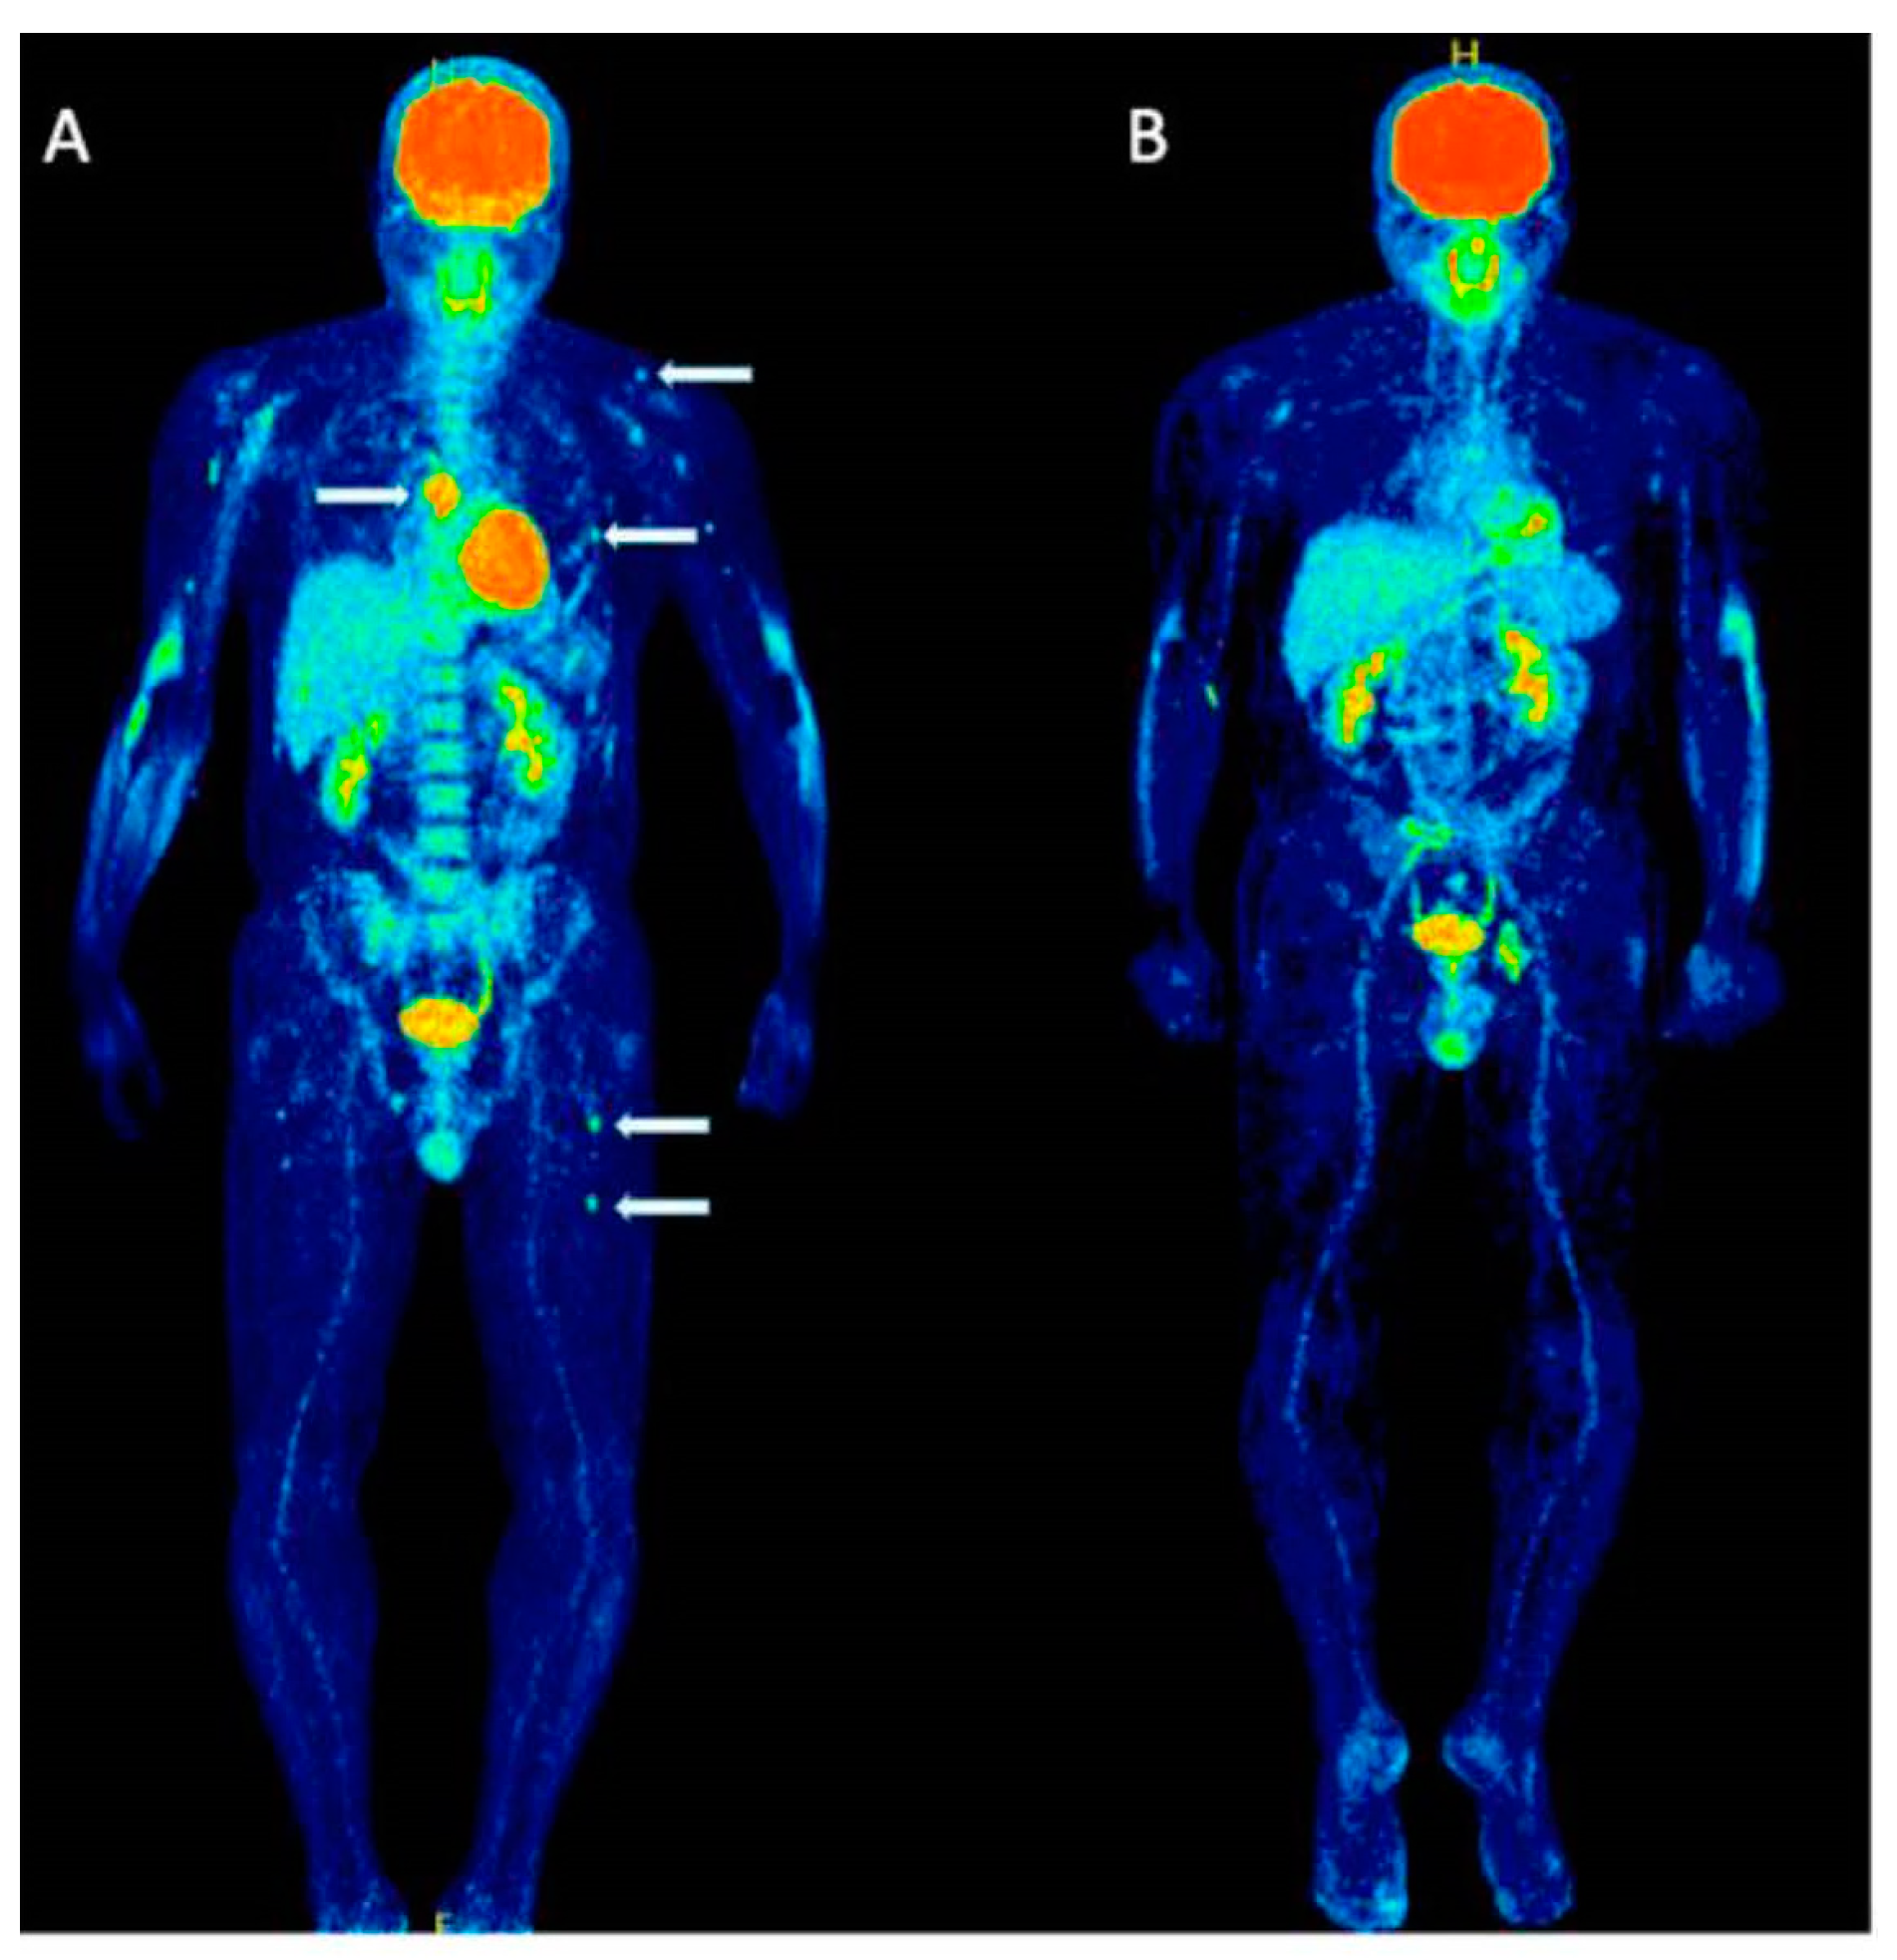

4. Importance of [18F]FDG PET/CT in Assessing Treatment Efficacy

4.2. Assessment of Myeloma Patients after Treatment

5. Identification of Minimal Residual Disease (MRD) in Myeloma

11. Italian Myeloma Criteria for Pet Use: IMPeTUs